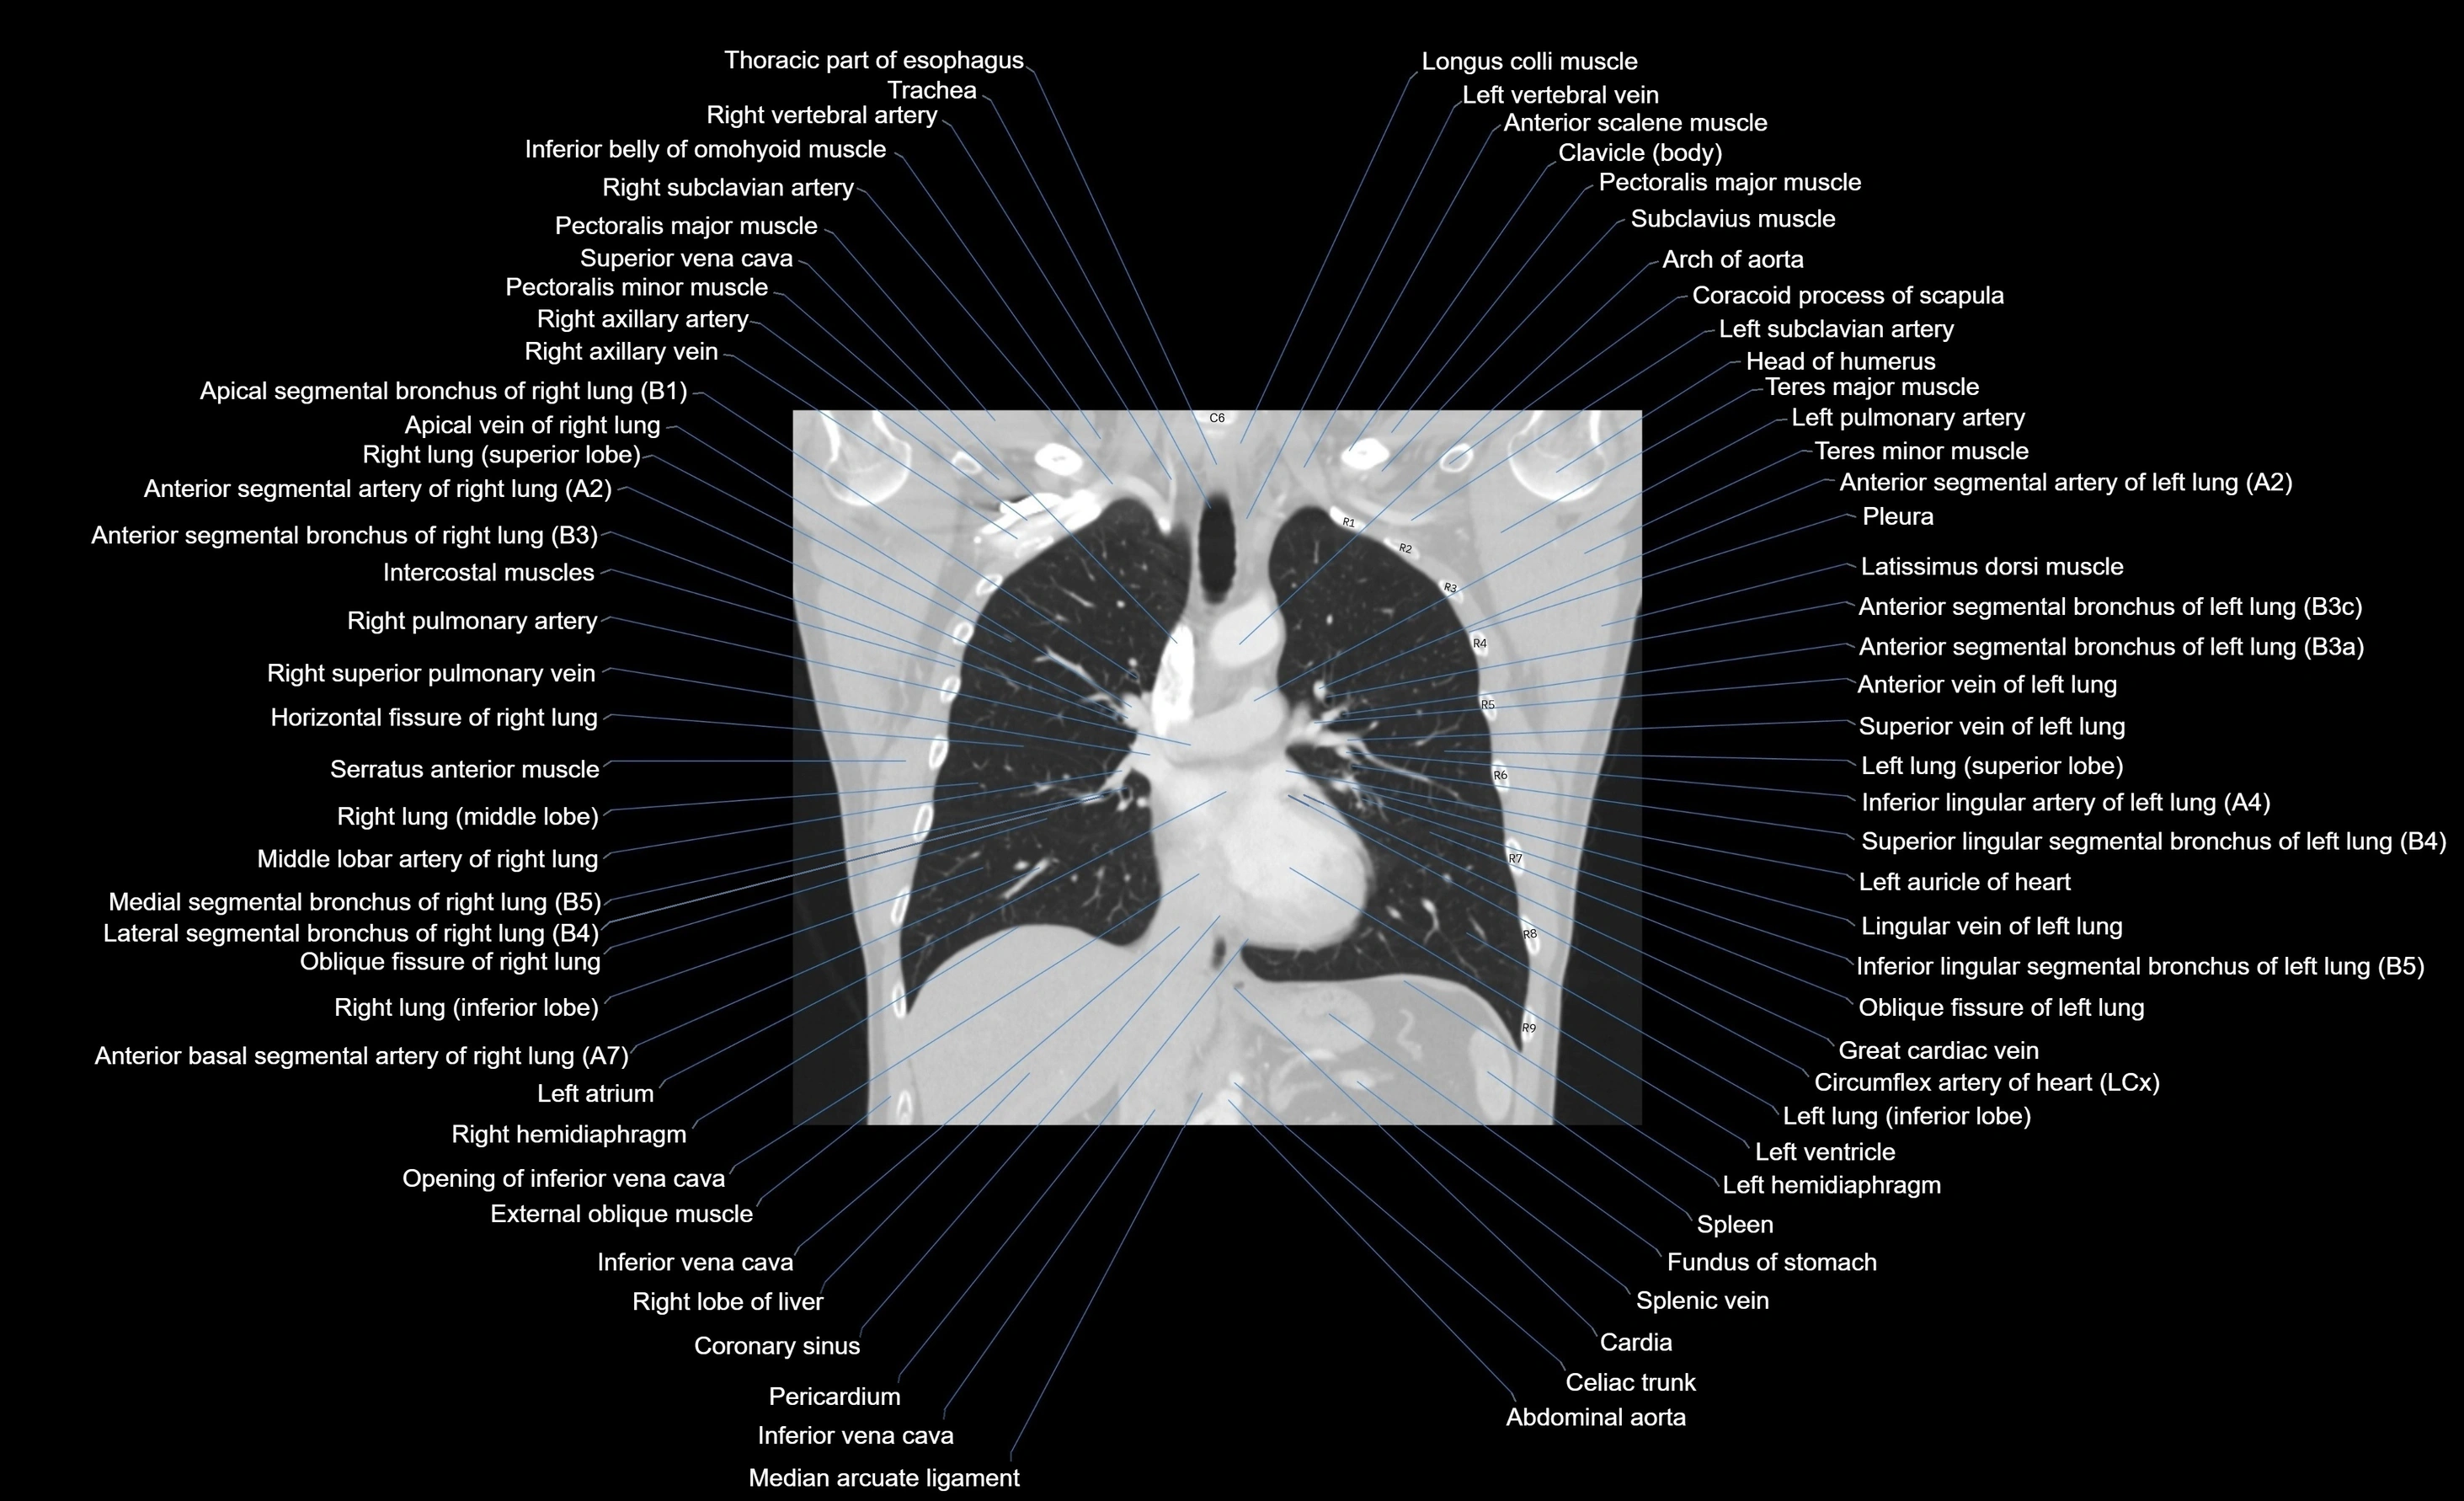

CT images